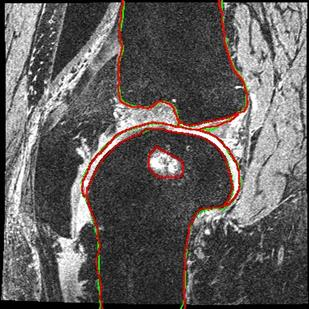

Direct automatic segmentation of objects from 3D medical imaging, such as magnetic resonance (MR) imaging, is challenging as it often involves accurately identifying a number of individual objects with complex geometries within a large volume under investigation. To address these challenges, most deep learning approaches typically enhance their learning capability by substantially increasing the complexity or the number of trainable parameters within their models. Consequently, these models generally require long inference time on standard workstations operating clinical MR systems and are restricted to high-performance computing hardware due to their large memory requirement. Further, to fit 3D dataset through these large models using limited computer memory, trade-off techniques such as patch-wise training are often used which sacrifice the fine-scale geometric information from input images which could be clinically significant for diagnostic purposes. To address these challenges, we present a compact convolutional neural network with a shallow memory footprint to efficiently reduce the number of model parameters required for state-of-art performance. This is critical for practical employment as most clinical environments only have low-end hardware with limited computing power and memory. The proposed network can maintain data integrity by directly processing large full-size 3D input volumes with no patches required and significantly reduces the computational time required for both training and inference. We also propose a novel loss function with extra shape constraint to improve the accuracy for imbalanced classes in 3D MR images.

翻译:3D医学成像的物体,如磁共振成像(MR)成像的直接自动分离,具有挑战性,因为往往需要精确地确定大量调查中大量存在复杂地理不对称的单个物体。为了应对这些挑战,大多数深层学习方法通常会大大提高其模型内可训练参数的复杂性或数量,从而提高其学习能力。因此,这些模型一般需要在运行临床MR系统的标准工作站上花很长的推断时间,并限于高性能的计算机硬件,因为它们的记忆要求很大。此外,要在这些大型模型中安装3D数据集,还要利用有限的计算机记忆,经常使用交换技术,例如补对称培训等,以牺牲从对诊断目的具有临床重要性的投入图像中获得的精细比例的几何地理信息。为了应对这些挑战,我们提出一个具有浅度记忆足迹的银色网络,以有效减少为状态性能所需的模型参数数量。这对于实际就业至关重要,因为大多数临床环境只有低端硬件,计算机功能和记忆有限。拟议的网络可以通过直接处理全尺寸三维化技术来保持数据的完整性,直接处理全尺寸的全尺寸三维的图像,从而大幅改进所需的超度变压的磁度计算。